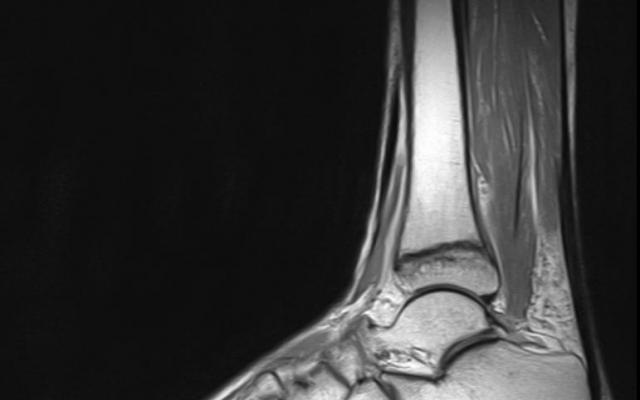

Dit artikel is alleen beschikbaar als PDF.Lees de PDF Artikelinformatie Online verschenen op 25 februari 1961 Citeer dit artikel als Ned Tijdschr Geneeskd. 1961;105:957 Heb je nog vragen na het lezen van dit artikel? Check onze AI-tool en verbaas je over de antwoorden. ASK NTVG Ook interessant Onderzoek De behandeling van wandelblaren Diagnose in beeld Een fanatieke wandelaarster met een pijnlijke enkel Beeldquiz Een fanatieke wandelaarster met een pijnlijke enkel Meer gerelateerd … Reacties Login om een reactie te plaatsen